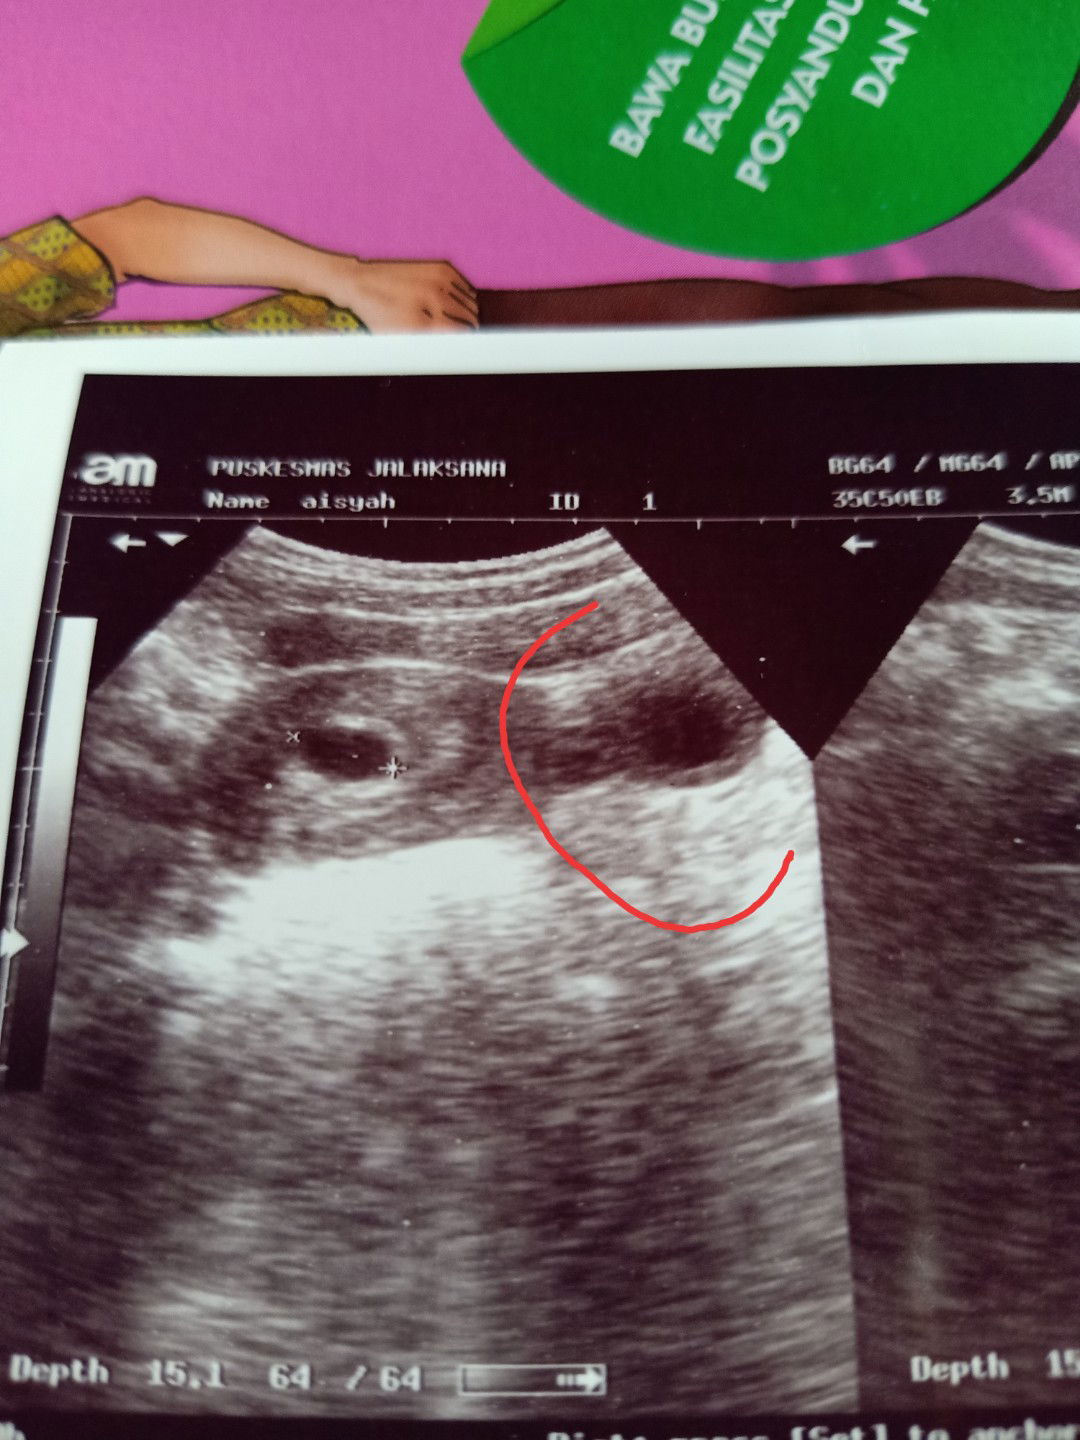

Saya takut banget yang di lingkaran merah itu apa ya ? Kata dokter di puskesmas ny tanya langsung aja ke dokter kandungan . Tp saya belum sempet .